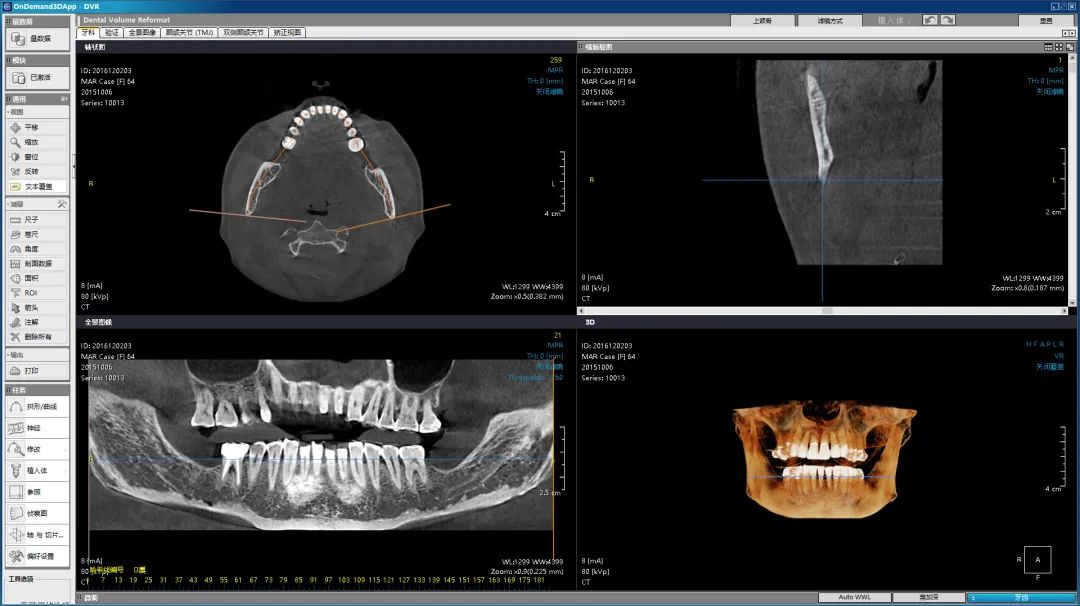

2021年中华口腔医学会第23次全国口腔医学学术会议暨2021中国国际口腔设备器材博览会上,在博恩登特最新的口腔CBCT体验区,智能3D全景技术叠加AI多轨迹聚焦威力全景技术的高质量CT影像吸引了不少口腔从业者驻足。“图像直观,操作简便,曲线CT的影像去伪影功能强,能在3D图像上很清晰地看到牙列排列情况。”参观者说。

每一项高端技术的突破,都如同在荒漠上开垦田地。比如,对于口腔CBCT来说,影像质量的好坏决定着市场对产品的认可度,口腔CBCT的硬件方面已趋于成熟,真正难的是软件的开发与更新迭代,研发团队成立之初就面临了极大的困境。当时国内在降低辐射剂量、金属伪影去除、超快速扫描、扩大有效视野方面都比较薄弱,难以突破核心图像重建算法,CBCT产品的影像质量一直不过关。“当时,卡脖子问题一直无法解决,压力非常大,每天都加班到深夜,有的同事甚至直接睡在公司。”CT研发总监杨振华回忆道。

影响对比

为了解决难题,田方俊1年里8次前往美国芝加哥大学医学院,希望得到医学影像、图像重建算法等领域的权威专家的帮助。“我当时一心想打造属于中国人的民族品牌,也许是我的这份坚持打动了专家,我们的研发团队和专家团队在美国共同设立研发中心,最终我们的核心图像重建算法研究有了质的突破。”田方俊介绍。